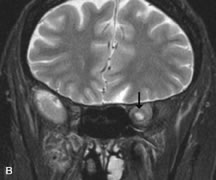

PATIENT PREPARATION Before MRI is performed, patients must be screened and prepared to avoid the potential hazards associated with the strong magnetic field. Patients who have ferrous aneurysm clips or cardiac pacemakers, who depend on life-support equipment, or who retain a possible metallic intraocular foreign body are not candidates for this imaging modality. MRI cannot be performed on obese patients who cannot fit into the bore of the magnet. Patients who are claustrophobic may not tolerate a prolonged period of study within the confines of the magnet, whereas others might do well if given a mild sedative. All worn metallic objects (e.g., necklaces, watches) should be taken off, credit cards set aside, and eye makeup removed before entering the room containing the magnet.5,20,34,35,36 NORMAL ORBITAL ANATOMY T1-weighted images provide the best anatomic details of the orbit because they display superior contrast resolution between normal structures (see Fig. 8). The vitreous has a long T1, resulting in an intermediate signal similar to brain, whereas the crystalline lens and sclera appear dark because of a longer T1 and short T2. The extraocular muscles, like all skeletal muscles, demonstrate a moderately long T1 and short T2 and highly contrast with the intense signal of the surrounding orbital fat (adipose tissue has an extremely short T1). The lacrimal glands appear as mottled areas of reduced intensity of the signal from the orbital fat in the lacrimal fossa. The optic nerves are seen with the same signal intensity as brain white matter and are hypointense relative to the orbital fat because their Tl is longer than the Tl of fat but shorter than the Tl of water. Cortical bone is not well delineated because it contains little free water, yielding minimal signal in MRI, and thus appears dark on all pulse sequences. This feature explains why MR images of the orbital apex and intracanalicular portion of the optic nerves are superior to comparable CT scans. Partial volume averaging of the bones in these regions obscures soft tissue details on CT images, whereas MRI reveals the signals only from the soft tissue structures with no cortical bone input. Bone marrow, on the other hand, is seen as a relatively intense signal because of its high fat content (see Fig. 8).37,38 T2-weighted pulse sequences are not ideal for imaging normal anatomy; however, they are particularly useful in revealing pathologic conditions (see Fig. 9). T2-weighted studies are most easily recognized by a bright vitreous signal. ORBITAL DISEASES Vascular Lesions Cavernous hemangiomas appear as well-circumscribed, smooth, usually intraconal masses that are isointense to muscle on T1-weighted images and hyperintense on T2-weighted images (Fig. 12). Patchy early enhancement is typically followed by diffuse, more homogeneous enhancement.39 The internal architecture of the mass, including septation and internal vasculature, may often be appreciated with high-quality orbital imaging.40 Lymphangiomas consist of ectatic vascular channels within a connective tissue stoma with varying degrees of lymphoid cellularity. On MRI, these tumors are typically poorly circumscribed, multicompartmental, and heterogeneous, often showing cystic dilations with fluid levels (Fig. 13). The signal characteristics within lymphangiomas vary considerably, reflecting cystic and solid components and the varying paramagnetic characteristics of blood at different stages of degradation.40–42 Acute hemorrhage appears hypointense on both T1- and T2-weighted formats. Methemoglobin present in subacute hemorrhage (3 to 14 days) leads to hyperintense signal on both T1- and T2-weighted images.41 A small percentage of lymphangiomas appear radiologically indistinct from orbital cavernous hemangiomas.43 Orbital varices are venous malformations that expand with increased systemic venous pressure, such as with Valsalva maneuvers. Because rapid acquisition of images during a Valsalva maneuver is important in imaging such a lesion, conventional or spiral CT is currently the modality of choice.44 MRI is an excellent modality for demonstrating enlargement of the cavernous sinus and dilation of the superior ophthalmic vein in patients with high-flow carotid-cavernous fistulas (Fig. 14).37MRA may be helpful in the evaluation of the venous outflow pattern. The rapidly flowing blood in these vascular structures carries the excited protons out of the section before they can be imaged, resulting in their dark appearance.5 In low-flow dural arteriovenous malformations, MRA may help define the arterial feeding vessels.45 Neural Lesions MRI is more effective than CT in delineating the intracranial optic nerves, chiasm, and optic tracts and, for this reason, is the preferred imaging modality in the evaluation of optic nerve disorders. The spatial relationships and image contrast of the orbital tissues with intraorbital optic nerve tumors is comparable between the two imaging modalities. The normal nerve is isointense to brain and appears enlarged and kinked owing to infiltration of an optic nerve glioma on T1-weighted images. Gliomas appear hyperintense on T2-weighted images and may be heterogeneous owing to cystic areas within the tumor. Contrast enhancement is variable.46 Intraorbital and intracranial optic nerve sheath meningiomas are usually isointense to cortical gray matter on Tl-weighted images and remain isointense on proton density studies (Fig. 15). Gd-DTPA is useful in delineating the intracranial extension of optic nerve meningiomas.7,47 The hyperostosis of bone and calcification associated with meningiomas are not demonstrated as well on MRI studies as on CT scans.20,37 Gd-DTPA–enhanced MRI also appears promising in the study of the permeability of the blood–brain barrier in selected optic neuropathies.22,48 MRI may reveal an enlarged optic nerve and some degree of contrast enhancement in cases of optic neuritis.49 Muscle Disorders Extraocular muscle enlargement in patients with thyroid-associated orbitopathy is demonstrated equally well with CT and MRI studies. However, the superior tissue contrast on MR images reveals better details of the relationships of the optic nerve to the thickened muscles at the orbital apex (Fig. 16).50 In addition, MRI may be able to differentiate between muscles that are enlarged as a result of edema and active inflammation and those enlarged because of fibrosis by their T2 relaxation times.21 Quantitative MRI was not found to be accurate in predicting the success of low-dose orbital irradiation.51 However, a muscular index relating the diameters of the rectus muscles to the bony orbital dimensions was useful in predicting optic nerve compression.52 MRI is also effective in imaging orbital tumors of mesenchymal origin, such as rhabdomyosarcoma, particularly in the assessment of extension into the anterior and middle cranial fossae (Fig. 17).37 The lack of any pathognomonic radiologic features necessitates rapid orbital biopsy when rhabdomyosarcoma is suspected. Osseous Lesions In general, CT is the imaging modality of choice when details of quantity and quality of bone are needed; however, abnormalities of bones can be detected indirectly by MRI. Cortical bone appears black (signal void) on MR images because of its low proton density and free-water content. The absence or discontinuity of the signal void of the orbital walls may represent bony destruction or fracture. Hyperostosis associated with prostate metastases or meningioma is visualized as areas of black smudging.50,53 Diseases in which the bone is replaced by pathologic tissues with a high free-water content, such as fibrous dysplasia, are well demonstrated on MRI. An intermediate signal intensity on T1-weighted images and hypointense signal on T2-weighted images is representative of fibrous dysplasia. Enhancement on post–Gd-DTPA MR scans is seen and is more evident in areas that are less mineralized.54 Cystic Lesions Dermoid cysts appear as rounded, well-defined lesions typically contiguous with an orbital bony suture. The high-intensity signal on T1-weighted images is attributed to the sebaceous-produced lipid contents (Fig. 18).31,50 Mucoceles may demonstrate a hypointense or hyperintense signal on MR images, depending on the concentration of proteinaceous or inflammatory fluid components. The integrity of the bony walls of the expanded sinus cavities cannot be assessed on MR as well as by CT.37,50,55,56 A high-signal intensity on Tl- and T2-weighted images is characteristic of orbital chronic hematic cysts because of the blood-breakdown products within the cysts.57 Trauma Although soft tissue relationships are usually better demonstrated on MRI, the evaluation of craniofacial bony trauma is preferable with CT. For example, prolapse of orbital fat through a fracture site and hemorrhage of adjacent tissues are demonstrated in an MR image, but the actual fractured bone is not imaged. Three-dimensional MRI of the orbit in subacute trauma has been described,58 although its precise role is not currently established. MRI has been suggested to be superior to CT in detecting intraorbital wooden foreign bodies.59,60 In a series of penetrating orbital injuries with organic foreign bodies, however, MRI was able to identify the foreign body in only four of seven cases.61 With an in vitro model for wood foreign body, McGuckin and colleagues concluded that CT was the imaging modality of choice.62 A careful history and, in selected cases, plain films to rule out a metallic foreign body are crucial before MRI is considered in patients with periocular trauma. MRI is particularly helpful in the detection and characterization of subperiosteal hematomas of the orbit (Fig. 19). They are most commonly seen in the subperiosteal space of the superior orbit as well-defined masses following a traumatic injury. The signal intensity varies depending on the acute, subacute, or chronic nature of the hematoma, based on the stage of blood degradation. Fresh hemorrhages are hypointense on T1-weighted images and hyperintense on T2 images. Hematomas that are 1 to 7 days old are hypointense on both T1- and T2-weighted images. T1-weighted images of hematomas more than a week old are hyperintense due to the oxidation of deoxyhemoglobin to methemoglobin, whereas the T2 images remain hypointense.63 Metastatic Tumors Breast carcinoma metastatic to the orbit has been demonstrated to be hypointense to the surrounding orbital fat on T1-weighted studies and hyperintense on T2-weighted images and has an affinity to the extraocular muscles (Fig. 20).50,64 The MRI characteristics of prostate carcinoma metastatic to the orbit have been described as involving the greater and lesser wing of the sphenoid, orbital roof, and optic canal. Diffuse bone hypertrophy with isointense or slightly hyperintense tissue on T1-weighted images represents the osteoblastic carcinomatous bone infiltration. Contrast enhancement is variable on T1-weighted and fat-suppressed images.65 Most other metastatic tumors also have a lower intensity signal on T1-weighted images and appear to displace or infiltrate normal orbital structures; however, their signal characteristics are variable on T2-weighted MR images.66 Many metastatic tumors demonstrate bright contrast enhancement with Gd-DTPA. Infectious Disorders MRI findings of preseptal and orbital cellulitis typically include increased signal intensities on T2-weighted images of the eyelids and orbital fat, respectively, due to the increased water content of the tissues. Since most cases of bacterial orbital cellulitis are associated with paranasal sinusitis, hyperintense signals of the affected sinuses may also be found on T2-weighted images as well as enhancement of polyps and granulation tissue on postgadolinium T1-weighted MR images. Subperiosteal abscess formation may occur due to contiguous spread of infection from the paranasal sinuses and appear on MRI as an area of intermediate signal on T1-weighted and proton-weighted MR images. The abscess may appear slightly hyperintense compared with muscle on T2-weighted scans with the necrotic contents having the greatest intensity.67 MRI and MRV are more sensitive than CT in revealing cavernous sinus thrombosis. Engorgement of the cavernous sinus, extraocular muscles, and ophthalmic veins is seen with hyperintensity of the thrombosed sinuses evident on all pulse sequences. The enlarged, thrombosed superior ophthalmic vein appears less hypointense than the normal contralateral ophthalmic vein, and hyperintensity within the lumen of the vessel may be seen on T1- and T2-weighted MR images.68 Inflammatory and Lymphoproliferative Lesions Inflammatory conditions of the orbit, both idiopathic (inflammatory pseudotumor) and those of known causes, have been found to be hypointense to fat and isointense to muscle on Tl-weighted studies and isointense or slightly hyperintense to fat on T2-weighted images (Fig. 21).50,64,69 The more fibrous or sclerosing varieties have less signal intensity on T2-weighted images. Marked enhancement is seen in pseudotumor infiltrates after gadolinium administration.70 The same signal characteristics are demonstrated in patients with Tolosa-Hunt syndrome, with mass lesions seen in the cavernous sinuses and orbital apices.71 Lymphomas have MRI characteristics similar to those of inflammatory lesions in that they are hypointense to fat and isointense to muscle on T1-weighted images (Fig. 22). They may appear hyperintense to fat on T2-weighted images, perhaps owing to less fibrosis than that seen in orbital inflammatory pseudotumor, although this is not a consistent finding.31,50,66 Lymphoid tumors typically enhance moderately after contrast injection. Unfortunately, studies have shown that tumor density and homogeneity are similar between inflammatory and malignant orbital infiltrates, and MRI cannot differentiate these lesions.72,73 Lacrimal Gland Tumors Lacrimal gland lesions present special problems in diagnosis and management. Pleomorphic adenoma (benign mixed tumor) should not be biopsied, but rather excised in toto. On the other hand, for lymphoma and inflammatory infiltrates, incisional biopsy is more appropriate than complete excision of the lacrimal gland. Thus, preoperative clinical and radiologic evaluation are especially crucial in planning appropriate surgical management. Pleomorphic adenomas demonstrate long T1 and T2 signal characteristics. They may show heterogeneity on T2-weighted images74 and moderate to marked enhancement with contrast.75 Signal characteristics of adenoid cystic carcinoma include hypointensity to fat on T1-weighted images, hyperintensity to fat with increased T2 weighting, and isointensity to fat on proton density-weighted studies (Fig. 23).31,75 Secondary bony alterations of the lacrimal fossa associated with lacrimal gland tumors, such as remodeling (benign mixed tumor) or destruction (adenoid cystic carcinoma), are seen indirectly on MR images; however, bone windows on CT scans provide better delineation of these changes. In contrast to the round or globular appearance of benign or malignant epithelial tumors of the lacrimal gland, lymphoproliferative tumors usually appear to be molding or draping onto the globe and the surrounding bony orbit. LACRIMAL DRAINAGE SYSTEM DISORDERS MRI with surface coils provides excellent spatial resolution and tissue-specific signal intensities of the lacrimal drainage system. These parameters have been found useful to more accurately demonstrate the extent of lesions in the lacrimal sac and differentiate long-standing mucoceles from solid tumors than CT.76 Physiologic studies in patients with tearing disorders now include MR dacryocystography, in which Gd-DTPA is either placed topically in the conjunctival fornix or injected by cannulation into the lacrimal sac. They provide a detailed morphologic and functional analysis of the lacrimal excretory system; however, they are no more sensitive than digital-subtraction dacryocystography or CT dacryocystography.77–79 INTRAOCULAR TUMORS On MRI, uveal melanomas have a typical appearance that helps to differentiate them from other primary and secondary intraocular tumors as well as choroidal detachments. Pigmented melanomas are hyperintense on Tl-weighted images, hypointense on T2-weighted studies, and hyperintense on proton density–weighted examinations (Fig. 24).30,31,50,80–82 These signal characteristics have been attributed to the paramagnetic properties of melanin because of stable free radicals that shorten the T1 and T2 relaxation times. Moderate enhancement is seen on postgadolinium T2-weighted images. Gadolinium-enhanced T1-weighted images are particularly sensitive in detecting choroidal melanomas.83 MRI may be less sensitive in detecting extrascleral extension of tumor than echography performed by an experienced ultrasonographer.84 Tumors metastatic to the choroid are hyperintense on T1- and T2-weighted images.24 The signal characteristics, however, may be similar to those seen with choroidal melanoma. Choroidal hemangiomas, on the other hand, have an intermediate signal on T1-weighted sequences and become hyperintense on T2-weighted images50 as well as proton density–weighted images.81 Retinoblastomas display moderate signal intensity on T1-weighted studies and a low signal on T2-weighted images.31,80,85 Calcification can be easily detected by CT and ocular ultrasonography but is not imaged by MRI.25,50 The presence of optic nerve involvement is best evaluated by MRI. ACQUIRED ANOPHTHALMIA When an eye is removed owing to tumor or trauma, an implant is typically placed in the intraconal space. MRI may be useful in defining the size, shape, and position of such orbital implants.86 Porous hydroxyapatite or polyethylene implants are preferred by many surgeons performing enucleation or evisceration. A porous implant offers the possibility of supporting a motility coupling peg to increase the movement of the overlying prosthesis. MRI with contrast is used by some surgeons to evaluate the degree of fibrovascular ingrowth in hydroxyapatite87 and porous polyethylene88 implants prior to motility peg placement. |